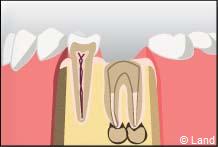

RECONSTITUTION MÉTHODE INDIRECTE AVEC UN INLAY-CORE OU FAUX MOIGNON.

L’inlay-core est une reconstitution métallique coulée qui restaure en partie la couronne naturelle de la dent. On utilise comme points d’ancrage les canaux radiculaires précédemment obturés lors du traitement conservateur.